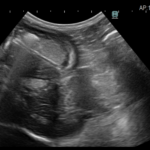

大阪府吹田市・豊中市・箕面市の皆さん。こんにちは。ESSE動物病院の院長 福間です。 今回は、誤食についての話を書いていこうと思います。今回は実際にあった話を書いていきます。 内容は、 ・来院…

最近「動物医療の実際を広めたい」と思っています。 なぜかというと、「獣医さんでそんなたくさんの検査ができるとは思っていなかった」「そんな選択肢を前の先生は言われてなかった」など、こんな話をよく耳にするからです。 これは単…